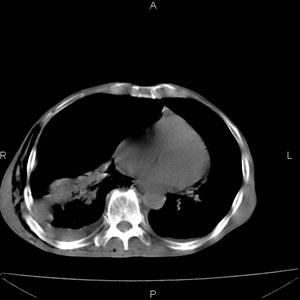

患者男,77岁,于3日前从树上摔下,头部查ct示蛛血,硬膜下出血,上腹部ct未见明显异常,右侧胸腔积液,左侧如常。肺部拍片示右侧肋骨多发骨折住院后今日来查肺部ct,我看到的是1。右侧胸腔血气胸并右肺上叶,中叶压缩性肺不张,2。右肺下叶肺挫伤并多发肋骨骨折,肌内及皮下积气3。左侧少量胸腔积液,我想请教的是3天前左侧胸腔里没有积液今天怎么出现了呢,是什么原因呢?请讨论。

支持楼主诊断。液体来源:1、血液成分,外伤所致。2、胸膜腔渗液—由于肺压缩、活动度下降,肯定胸膜吸收有问题,导致积液增多。

1、外伤出血需要一定的时间

2、气胸存在时间长了,产生的胸膜渗液